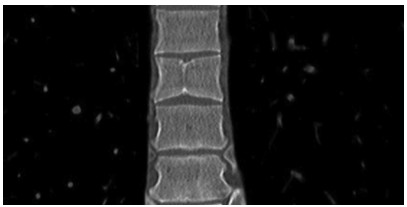

Postoperative complications of ex vivo liver resection combined with autologous liver transplantation in treatment of advanced hepatic alveolar echinococcosis at high altitude and related prevention and treatment strategies

Qingshan TIAN, Shaopei FENG, Yamin GUO, Xiumin HAN, Shunyun ZHAO, Chengjie YE, Yongde AN, Shile WU, Xiangqian WANG, Haibo ZHENG, Wenjun ZHU, Jide A, Wei GAO, Hongshuai PAN

2021, 37(9): 2153-2160. DOI: 10.3969/j.issn.1001-5256.2021.09.029

Abstract(1294) HTML (489) PDF (3321KB)(53)

Abstract:

Objective  To investigate the postoperative complications of ex vivo liver resection combined with autologous liver transplantation in the treatment of end-stage hepatic alveolar echinococcosis at high altitude and related prevention and treatment strategies.  Methods  Surgical data and follow-up data were collected from 11 patients with end-stage hepatic alveolar echinococcosis who underwent autologous liver transplantation in Qinghai People's Hospital from January 2013 to March 2019, and intraoperative and postoperative conditions were analyzed.  Results  All 11 patients underwent autologous liver transplantation successfully, without intraoperative death, among whom 2(18.18%) underwent hemi-extracorporeal hepatectomy and 9 (81.82%) underwent total extracorporeal hepatectomy. For the reconstruction of the retrohepatic inferior vena cava, 2 patients (18.18%) underwent reconstruction with the autologous great saphenous vein, 4 patients (36.36%) underwent reconstruction with artificial vessels, and the autologous retrohepatic inferior vena cava was preserved in 5 patients (45.45%). For biliary reconstruction, 8 patients (72.73%) underwent choledochoenterostomy and 3 (27.27%) underwent choledochocholedochostomy. The main postoperative complications of the 11 patients included bleeding in 2 patients (18.18%), bile leakage and abdominal infection in 4 patients (36.36%), bilioenteric anastomotic stenosis in 1 patient (9.09%), thrombus in 2 patients (18.18%), pulmonary infection and pleural effusion in 2 patients (18.18%), and echinococcosis recurrence in 1 patient (9.09%). Of all 11 patients, 2 (18.18%) died during the perioperative period, and the other 9 patients (81.82%) were improved and discharged.  Conclusion  Bleeding, biliary complications, and infection are the main causes of death in patients undergoing autologous liver transplantation at high altitude. An accurate understanding of surgical indication, careful multidisciplinary evaluation before surgery, superb operation during surgery, standardized surgical procedures, and fine perioperative management are the key to reducing perioperative mortality, avoiding and reducing postoperative complications, and achieving good long-term survival in patients undergoing autologous liver transplantation.